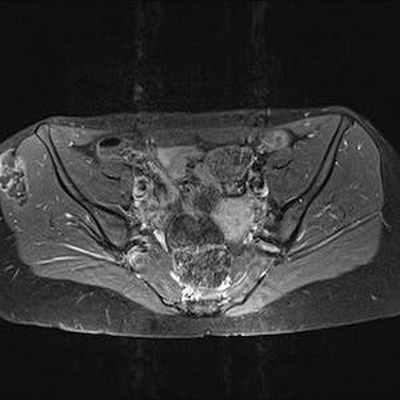

>>>Опухоль крыла правой подвздошной кости, диагностированная четыре года назад, обнаруженная на рентгеновском снимке, сделанном в рамках медосмотра подвздошной массы. Появление болей при пальпации и увеличение размера опухоли.

>>>Рентгенография: Экзостоз на широкой ножке. Тонкие очаги обызвествления вокруг поражения, но не всплошную, подозрительные.

КТ: контур периферического кортикального слоя не прерывается на границе с кортикальным слоем подвздошной кости. Хорошо различимая трабекулярная структура указывает на остеогенный экзостоз.

Свидетельствует о наличии хрящевого обызвествления, захватывающего, по-видимому, соседние мягкие ткани.

МРТ: чётко видимая хрящевая шапочка, имеющая геперинтенсивный сигнал на T2 (DP)-ВИ и изоинтенсивный сигнал на Т1-ВИ, неправильной формы и очень плотная (23 мм), принимающая дольчатый вид, вызывающая подозрение на саркоматозную дегенерацию. Периферическое повышение сигнала после инъекции.

IRM Pelvis Axial Pondération DP